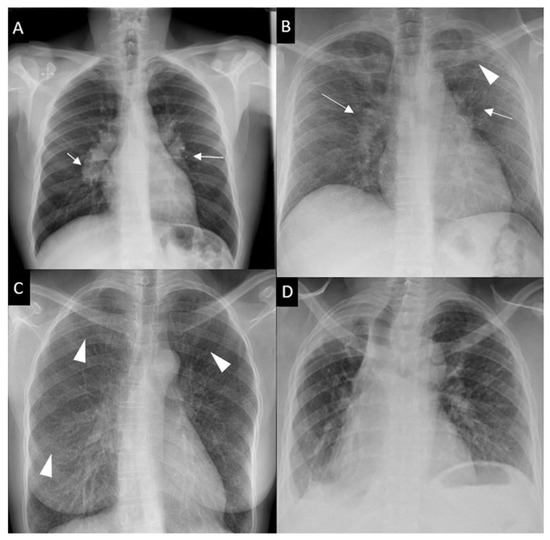

Respiratory symptoms are found at presentation in 30–53% of patients; cough in 27–53%, dyspnea in 18–51% and chest pain in 9–23% [16][30][31]. Chronic dyspnea is most frequently seen in patients with a delayed diagnosis, such as in the 10% of patients diagnosed with sarcoidosis-related lung fibrosis [9]. Bilateral perihilar lymphadenopathy, which is most frequently mediastinal lymphadenopathy [32] and perilymphatic pulmonary nodules predominantly seen in the upper lobe are the most typical imaging findings. Scadding’s classification defines five stages of sarcoidosis on a CXR (Figure 1).

Figure 1. Chest x-ray (CXR) staging system. Stage 0-normal CXR (not shown); (A) Stage 1-bilateral hilar lymphadenopathy (white arrows); (B) Stage 2-bilateral hilar lymphadenopathy (white arrows) and pulmonary infiltrates in upper lobes (white arrowhead); (C) Stage 3-pulmonary infiltrates (white arrowhead) without bilateral hilar lymphadenopathy; (D) Stage 4-pulmonary fibrosis.

This system was developed prior to computed tomography (CT) and is widely used for its prognostic value. Mediastinal lymphadenopathy, especially right paratracheal and aorto-pulmonary locations, are commonly observed on chest CT. Calcifications [33] of lymph nodes may occur in sarcoidosis; they are usually chalky, focal and tend to be bilateral when present [33]. Chest CT is much more sensitive than CXR for the detection of lung nodules and subtle fibrosis. Pulmonary nodules tend to be tiny, usually termed “micronodules” ranging from 2 to 5 mm, typically located along the bronchovascular bundles, interlobular septa, interlobar fissures and subpleural regions, which constitute the “perilymphatic distribution (Figure 2A). Pulmonary fibrotic changes may be a dominant feature with typical features of architectural distortion, volume loss and bronchiectasis, which tend to predominate in the middle and upper lung zones (Figure 2B). Recently, the “dark lymph node” or the “cluster of black pearls” sign (defined by tiny round nodules each measuring 1–2 mm which are seen uniformly distributed throughout all or part of the lymph node) has been described as relatively specific of sarcoidosis with negative and positive predictive values of 96 and 91%, respectively [34]. The “galaxy” sign is also highly suggestive for sarcoidosis; it consists of a large nodule, usually with irregular boundaries, surrounded by a border of tiny satellite nodules. Alveolar, pseudo-alveolar consolidations, or diffuse ground glass are rarely the cause of sarcoidosis-associated radiological abnormalities [35].